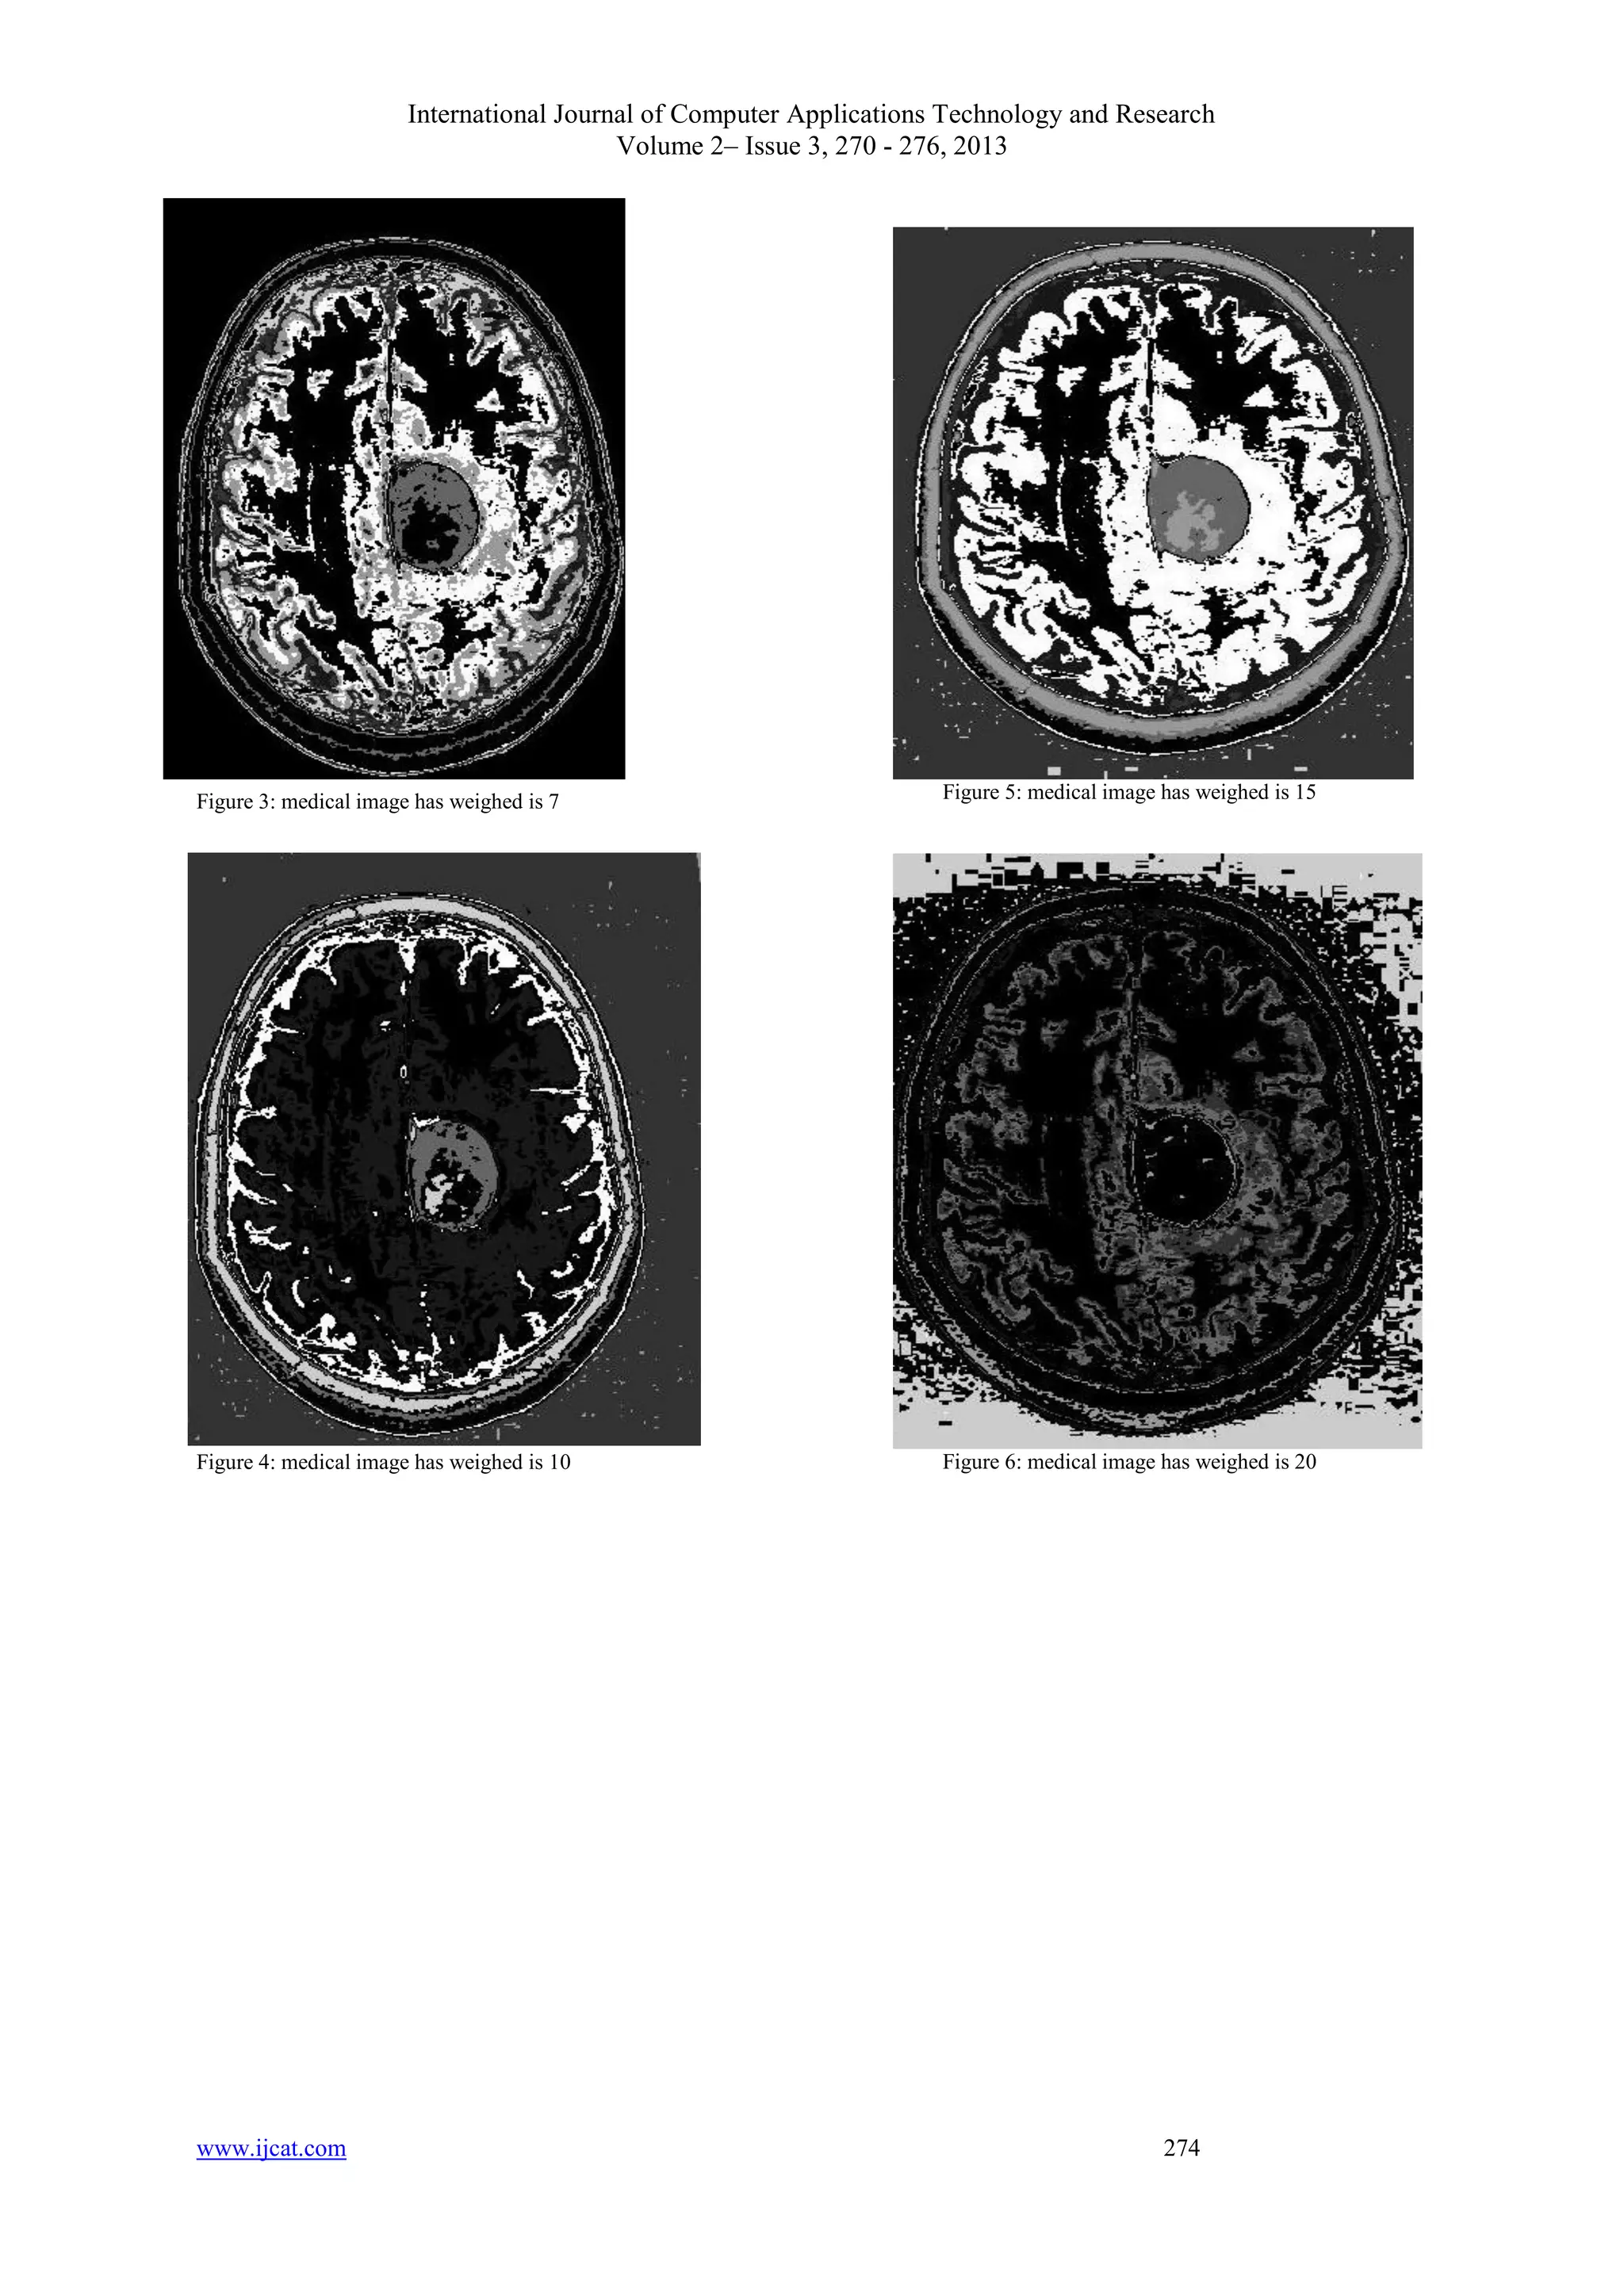

The experiments on the medical images

medical images. In the Figure 2 we can see the

original medical images. Figure 3 shows the cluster

index images by the applying variable weight is 7

in Figure 2. Now compare it with Figure 4, which

are cluster index images by applying variable

weighting is 10. We can see that segmentation of

areas is good in Figure 5 than in other figures. The

Figure 5 has variable weighting in 15. The Figure 6

is another resulted image an applying weight is 20.

Comparing those images the Figure 5 is better than

another. It has variable weighted is 15. Now we

Figure 3: medical image has weighed is 7

Figure 4: medical image has weighed is 10

Figure 5: medical image has weighed is 15

Figure 6: medical image has weighed is 20